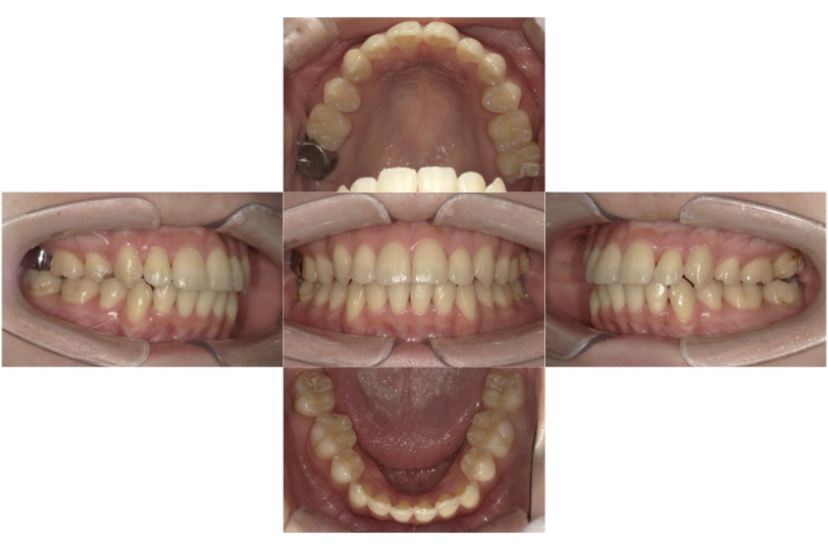

BEFORE

AFTER

上下顎叢生、反対咬合(上下の前歯のガタガタ、若干受け口)のケースです。

装置はラビアル(上下表側)で、上下顎の小臼歯を4本抜歯を行っています。抜歯したスペースを使って、上下の叢生改善と前歯の受け口の改善を行っています。

主訴 前歯のガタガタを治したい。

年齢・性別 45歳 女性

治療方針 抜歯スペースを利用して上前歯の叢生(ガタガタ)の改善と受け口の改善

抜歯部位 上顎左右第一小臼歯、下顎左右第二小臼歯

使用装置 ラビアル(上下表側)、顎間ゴム

治療期間 2年6か月

治療回数 20回

リテーナー クリアリテーナー